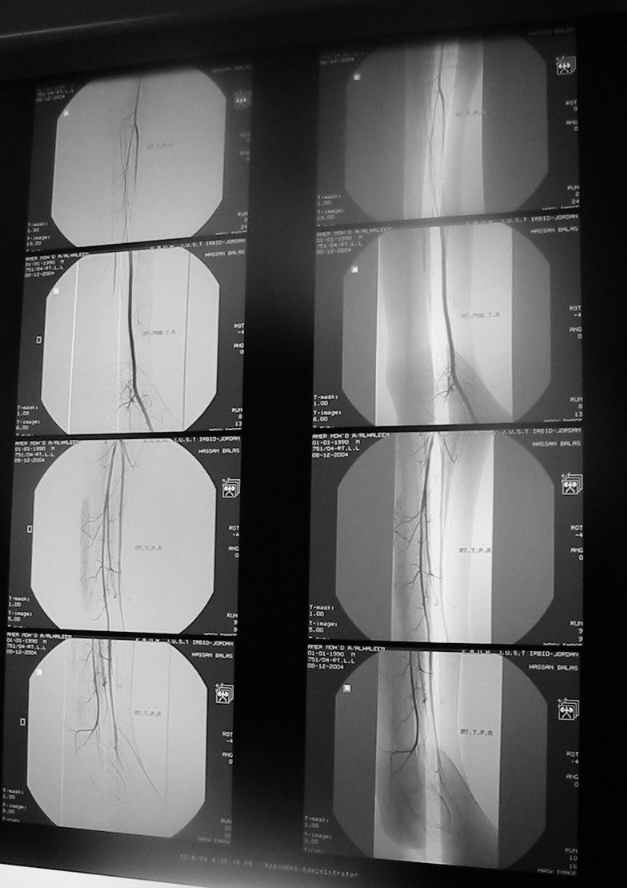

Судя по представленным фото и Рг граммам, у 13 летнего ребенка врождённая гемимелия большеберцовой кости, таранно-пяточный синостоз Из-за отставания в росте большеберцовой кости (остутствует дистальный эпифиз с зоной роста) произошла компенсаторная гиперофия малоберцовой кости, на которую приходится основная нагрузка (спонтанная тибиализация малоберцовой кости). Как результат дисбаланса осевого роста вторично возникла эквино-варусная деформация стопы. Продолжающийся рост ребёнка (до естественного закрытия зон роста) будет приводить к усугублению деформации по приведенным выше причинам.

Своё наблюдение только одно (ребёнка наблюдали и продолжаем наблюдать с рождения) и дважды оперировали: 1 этап выполнили проксимальный тиб/фиб фьюжн вторым этапом медиализация малоберцовой кости с таранно- малоберцовым синостозом и ещё предстоят этапы по удлинению тибиализированной малоберцовой кости.

В вашем случае я бы избрал следующую тактику:

Поднадкостничную остеотомию большеберцовой кости в средней трети с формированием синостоза с малоберцовой ( активно растущей) костью и второй уровень в области дистального тиб/фиб синдесмоза- достигается баланс роста( средне-медиальный и латеральный отделы) в области измененного голеностопного сустава. Коррекция эквино-варусной деформации стопы в аппарате после чрезкожной сегментарной тенотомии ахилова сухожилия. Дело

кропотливое и длительное.